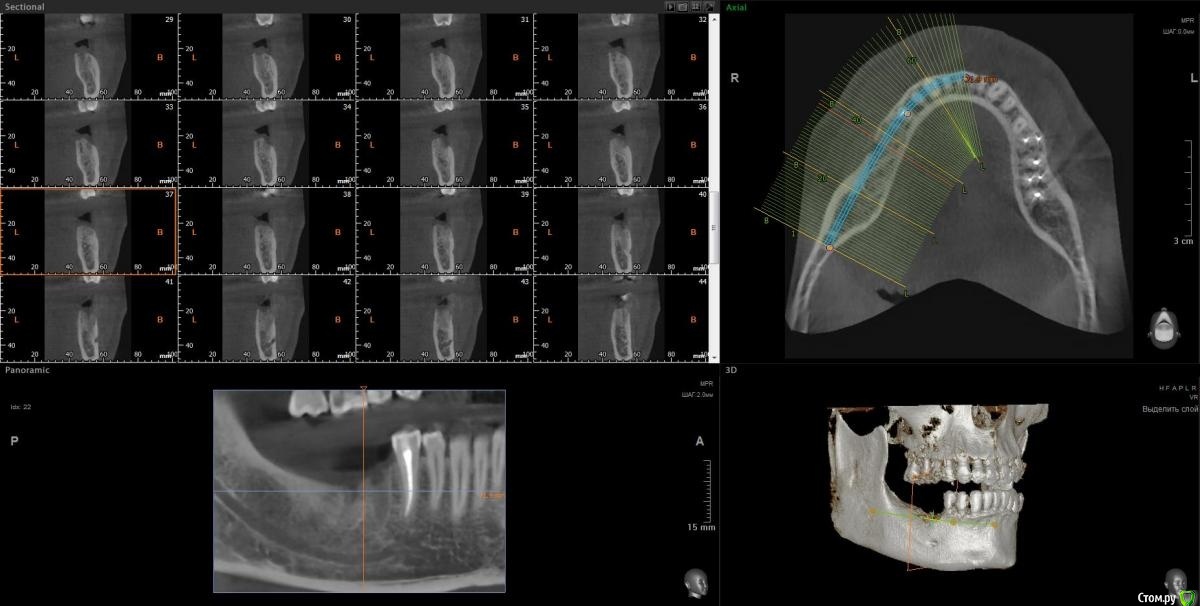

Vords Опубликовано 20 ноября, 2020 Поделиться Опубликовано 20 ноября, 2020 Доброго дня, форумчане. Прошу прощения за беспокойство. Хотел бы попытать счастье на форуме, поскольку все проведенные до этого консультации результатов не дали (( В общем ситуация такая: В начале сентября была неудачная попытка имплантации 46 и 47 зубов. 46 был удален и поставлены импланты nobel сразу в 46 и 47. В результате образовалась большая гематома и 2 недели были достаточно сильные боли в результате которых импланты были извлечены. После этого боль стала значительно более терпима и с ней я живу до сегодняшнего дня. И вроде уже через 20 дней нужно идти на вторую попытку имплантации, но боль еще не прошла. Никто (несколько терапевтов, имплантологов на КТ не видят причин для такой боли) - и идей ни у кого нет (( Было предположение, что отдает 45, так как очень сильно оголились корни после удаления 46 и его депульпировали, но боль не прошла. На данный момент идей совсем не осталось (кроме мифической идеи, что, возможно, 6 зуб сверху имеет пульпит (по теням на КТ) и отдает вниз. Я буду очень благодарен если у кого-то будут хоть какие-то идеи по этому вопросу, потому что жить с этой постоянной (пусть и не сильной) болью становится невозможно. Готов идти на очные консультации (но и было уже настолько много, что я, если честно, не уверен в их смысле). Ссылка на КТ https://yadi.sk/d/S3hKfHUWO-UTQg Сейчас пытаюсь разобраться как сделать качественные скрины нужных мест.Пока не выходит =(( Заранее благодарю. Ссылка на комментарий

Vords Опубликовано 1 декабря, 2020 Автор Поделиться Опубликовано 1 декабря, 2020 Осмелюсь еще раз побеспокоить, Вас, профессионалы. Ситуация развилась -16 вылечен (был кариес - обошлись без депульпирования), а на 15 и 14 поставлены циркониевые коронки. Но и боль никуда не делась снизу. Кроме того сейчас 45 зуб начал реагировать при жевании, а также неприятные ощущения при его чистке электрической зубной щеткой. Быть есть возможность у кого-то посмотреть его на КТ нет ли в нем каких-либо паталогий? быть может какой-то "скрытый канал" незапломбированный или что-то подобное. Или быть может такие боли в депульпированном зубе - это норма? Депульпировали 45 в середине ноября. Еще раз благодарю Вас за уделенное время. Ссылка на комментарий

Vords Опубликовано 1 декабря, 2020 Автор Поделиться Опубликовано 1 декабря, 2020 Ну и только что получил очень сильную боль при приеме горячей пищи(( Ссылка на комментарий

Марья Моревна Опубликовано 1 декабря, 2020 Поделиться Опубликовано 1 декабря, 2020 Возможно, в 16 зубе все-таки не кариес. Ссылка на комментарий